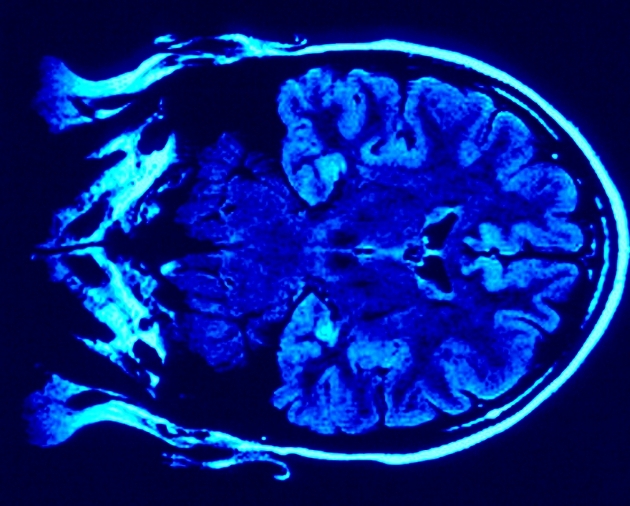

La neuroplasticidad es la capacidad que tienen nuestros cerebros de formar y reformar redes neuronales a partir de nuestras experiencias, es decir, la habilidad de moldearse con el aprendizaje.

Cuando estamos aprendiendo algo nuevo, se forman redes en nuestro cerebro a partir de neuronas que se comunican entre ellas a través de estructuras que permiten el pase de señales de una neurona a otra, conocidas como sinapsis. Una mejor comunicación entre neuronas está dada por un paso más eficiente de estas señales.

Cada vez que aprendemos o practicamos algo, estas conexiones se forman, o se refuerza la comunicación de conexiones existentes. Antiguamente se creía que las conexiones que se formaban durante nuestro crecimiento quedaban estáticas, pero hoy se sabe que la fuerza de estas conexiones puede variar de acuerdo con el uso o desuso de las mismas. Esta extraordinaria capacidad se conoce como plasticidad sináptica y es un concepto clave en el estudio del aprendizaje y la memoria.